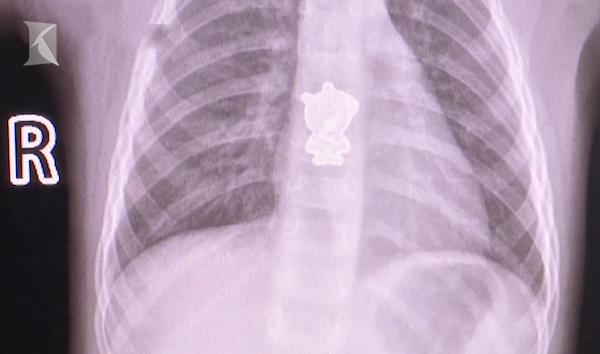

Sau khi chụp CT, bác sĩ và gia đình tá hỏa phát hiện một vật thể lạ có hình dáng "heo Peppa" bên trong thực quản của cô bé 2 tuổi.

Sau khi chụp chiếu, các bác sĩ soi thấy một vật thể có hình dáng như miếng sticker heo Peppa trong thực quản của cô bé. Mẹ của Tiểu Ngọc cho biết heo Peppa đó có lẽ là miếng dán trang trí trên đôi giày, nhưng rõ ràng nó đã được khâu rất chặt và không rõ con mình đã cho vào miệng lúc nào. Các bác sĩ đã tiến hành mổ nội soi thực quản và lấy vật thể ra khỏi người cô bé.